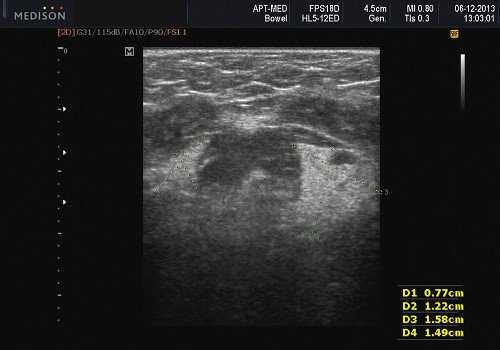

Рис. 3. Сиаладенит правой поднижнечелюстной слюнной железы.

Рис. 5. Камень протока поднижнечелюстной слюнной железы.

Рис. 6. Камень в паренхиме поднижнечелюстной слюнной железы.

Рис. 7. Камень в протоке поднижнечелюстной слюнной железы.